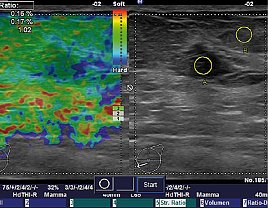

Der Ultraschall ist aus der modernen Radiologie nicht wegzudenken. Ohne Nebenwirkungen können so wichtige Informationen über Lymphnoten, Speicheldrüsen, Oberbauchorgane aber auch Gelenke, Sehnen und die Brustdrüse gewonnen werden. je nach Tiefe des zu untersuchenden Organs werden hierfür verschiedene Schallköpfe verwendet. Je höhe die Frequenz der Wellen hierbei ist, um so bessere und genauere Aussagen und Bilder kann man erhalten, allerdings ist die Eindringtiefe in den Körper für die Schallwellen geringer, je höher Frequent der Schallkopf ist. Deshalb braucht man im Alltag sowohl der Sectorschallkopf als auch einen möglichst hoch auflösenden Schallkopf. Wir haben mit einem linearen Schallkopf bis 14MHz, einem weiteren linearen bis 13 MHz und einem Sektorschallkopf bis 10MHz alle technischen Voraussetzungen für einen hochqualifizierten Ultraschall in der Radiologie, der ebenfalls ambulant und stationär angeboten wird. Besonderheit hierbei ist, dass durch die Elastographiesoftware die Härte eines tumorverdächtigen Befundes ermittelt werden kann, was häufig hilfreich ist, um zu entscheiden, ob es sich um einen gut- oder bösartigen Tumor handelt. Hierüber wurden verschiedene Arbeiten durch Prof. Malich publiziert. Als Alleinstellungsmerkmal ist der Ultraschall von Lymphknoten, Speicheldrüsen und dem Hoden als Kassenleistung an der Radiologie des Südharzklinikums abrechenbar neben den sonst üblichen sonografischen Untersuchungen. Auch über die Lymphknotensonografie wurden mehrere Publikationen veröffentlicht. Darüber hinaus kann man über die Nutzung des sogenannten Dopplereffekts die Durchblutung von Tumoren, Drüsen, Lymphknoten und Gefäßen beurteilt werden.